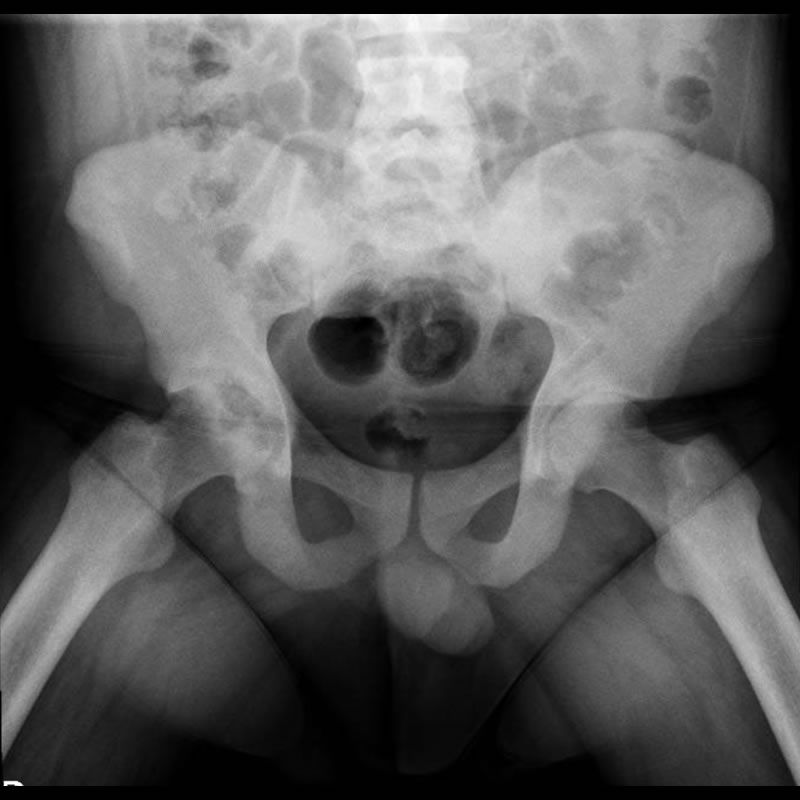

Agosto 2021. Sanatorio Allende Paciente de 29 años de edad con APP de AR, vitiligo y covid recuperado. MC: dolor en miembros inferiores a predominio derecho con impotencia funcional.